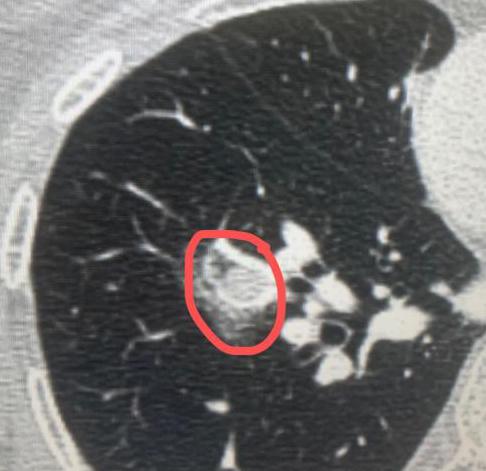

我的同行,一位 75 岁的医务工作者,6年前体检偶然查出的肺病灶,之后便一直处于观察状态。期间,大家普遍认为这只是肺大泡或肺气肿,并未过多警惕。 直到大概 4 年前,情况有了转折!当时他的太太因肺结节被确诊为早期肺癌,我为他太太主刀手术时,顺便仔细查看了他的肺部影像,当即提出一个不同的判断:这很可能是囊腔型肺癌,而非此前认为的良性病变。 今年,他再次复查,结果显示病灶较 2019 年明显增大 ——2019 年时病灶仅 1 公分,如今已长到两点几公分。 结合影像特征和病情进展,我判断早期肺癌的可能性极大,因此近期为他安排了手术。 其实,囊腔型肺癌近年来并不少见,仅这两个礼拜,我就接诊了十几例这类患者。很多人都会有疑问:为什么肺癌会呈现囊腔形态?囊腔型肺癌到底严重吗? 这里要跟大家说清楚:囊腔型肺癌的严重程度,关键看病灶内的软组织成分。如果软组织成分少,它的性质就类似原位癌或微浸润癌,恶性程度较低,预后也较好。 就像这位 75 岁的患者,虽然病灶体积增大了,但内部软组织成分很少,术后病理结果也证实是微浸润癌。 这类肺癌之所以会形成囊腔,核心原因是肿瘤细胞仅沿着肺泡壁生长,并不向外侵犯。在生长过程中,肿瘤细胞会产生一定张力,导致肺泡逐渐扩张,最终形成我们看到的囊腔形态。 之前还有病友特意打电话问我,说有人写文章说囊腔型肺癌很严重,为此十分担心。但事实上,大多数薄壁、软组织成分少的囊腔型肺癌,都属于早期病变,只要及时通过手术处理,术后通常不需要进行放化疗等后续治疗,治愈率很高。 当然,即便属于早期,一旦发现病灶有增大趋势,还是要尽早手术干预,避免病情进一步发展。[玫瑰][作揖]